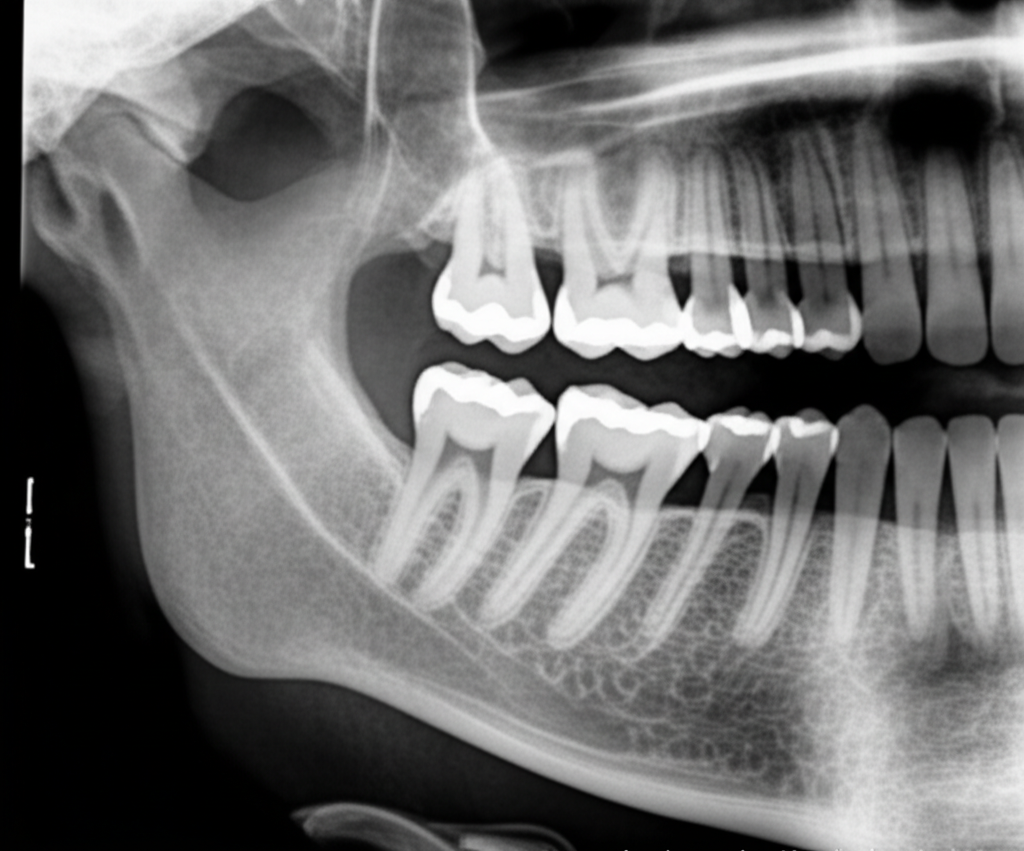

- 방사선 촬영비: X-ray 또는 CT 촬영을 통해 사랑니의 위치와 상태를 파악하는 비용입니다.

- 첨단 장비: 대학병원에서는 CT, 3D 프린팅 등 첨단 장비를 사용하여 사랑니의 위치와 신경과의 관계를 정확하게 파악하고, 수술 계획을 수립합니다. 이는 신경 손상 가능성을 최소화하고, 수술의 성공률을 높이는 데 기여합니다.

- 정확한 진단: 치과에 방문하여 구강 검진 및 방사선 촬영을 통해 사랑니의 상태를 정확하게 진단받아야 합니다. 의사와 충분히 상담하여 발치 여부를 결정하고, 수술 계획을 세워야 합니다.